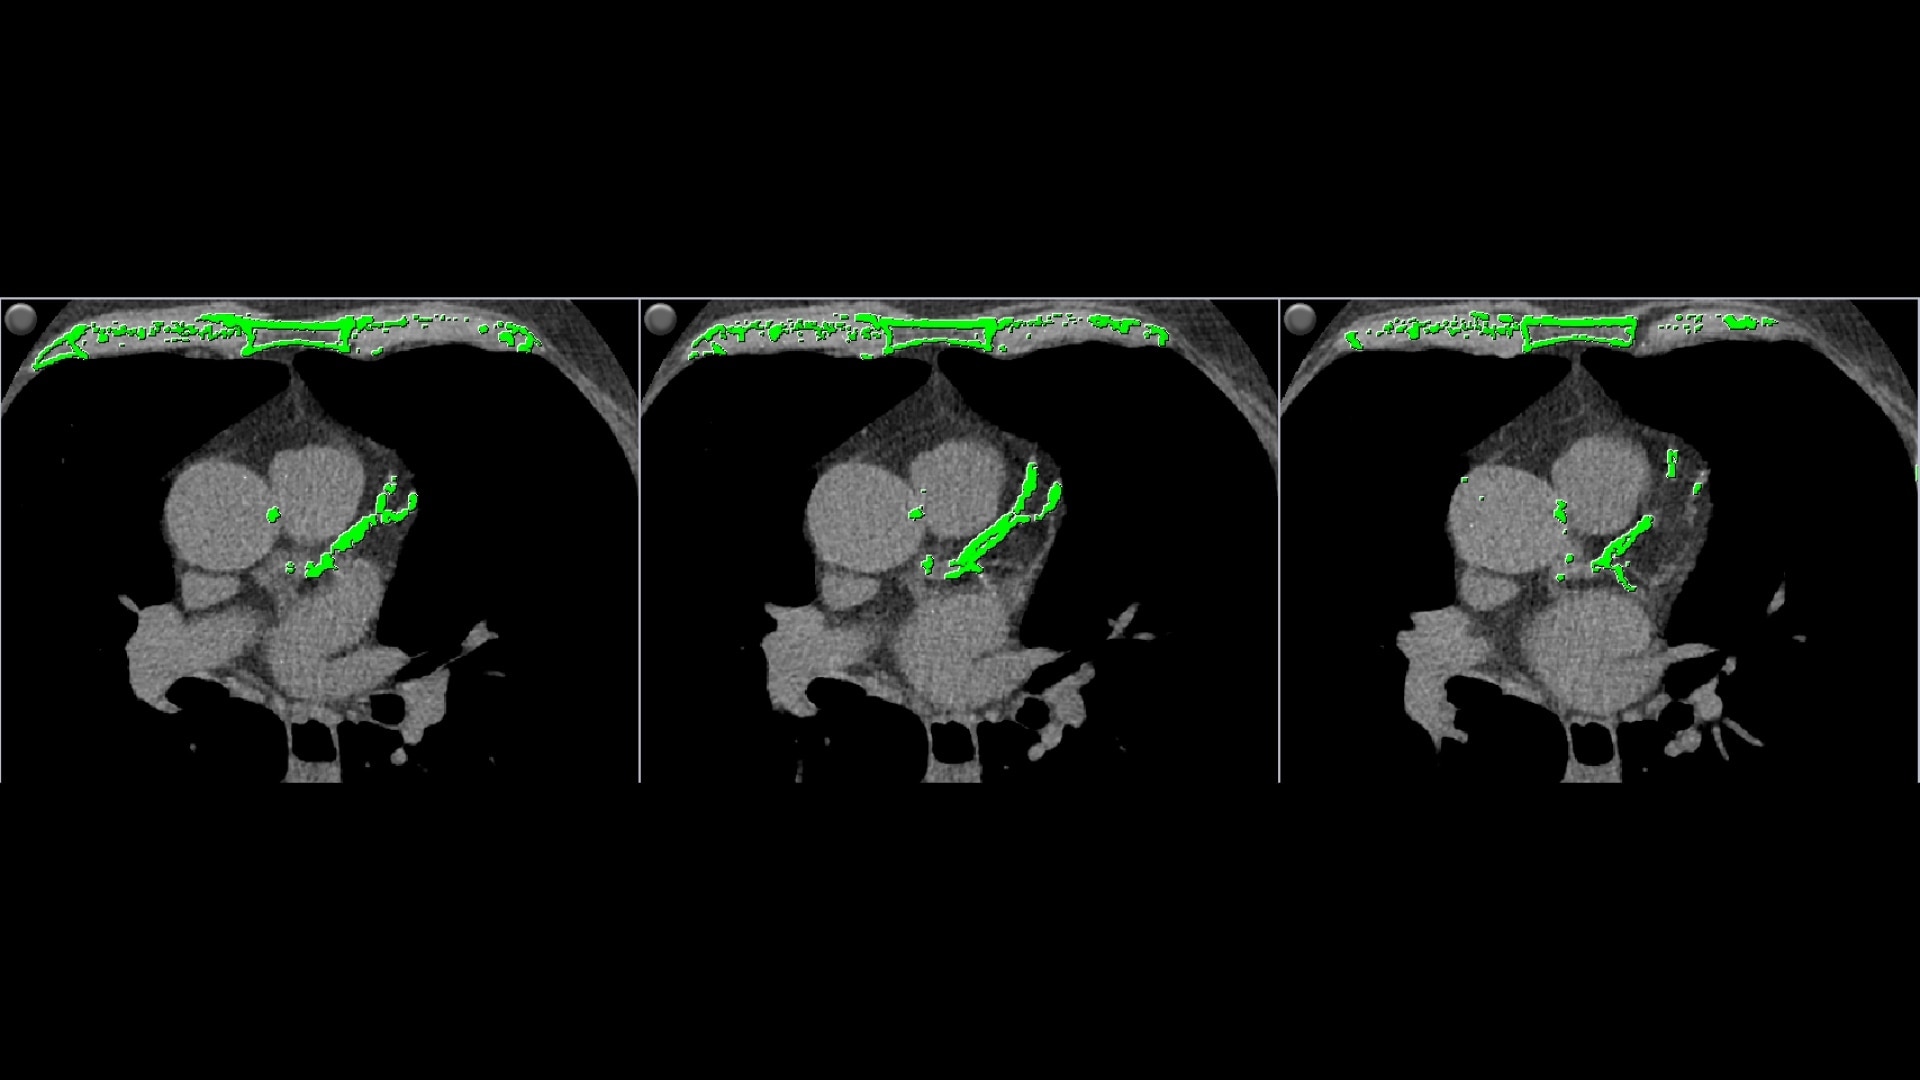

• Automatically detects calcium and highlights it in green

• Individual and aggregate scores are computed for each artery type

• Provides two methods of calcium scoring